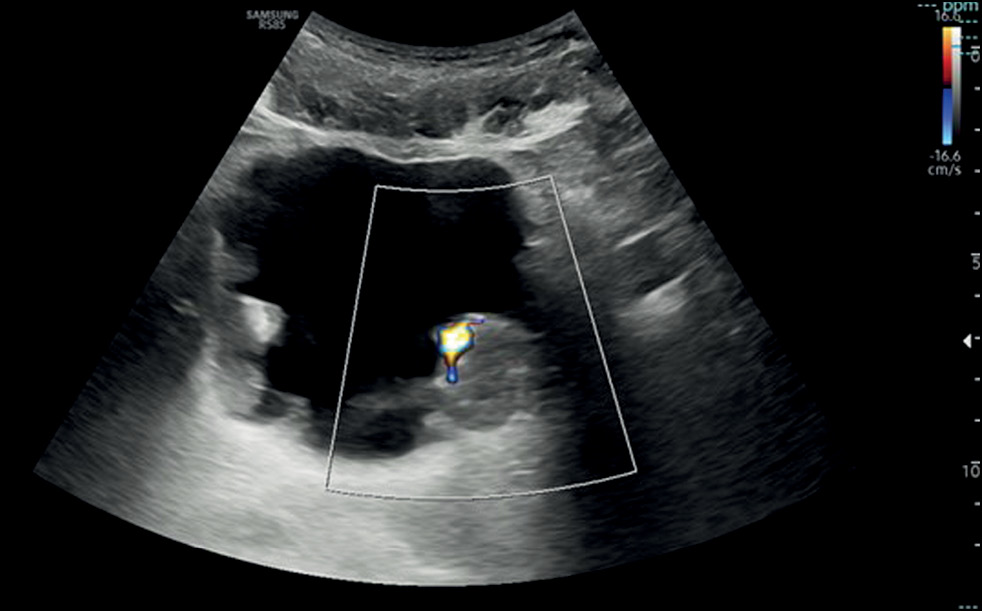

Conventional and innovative imaging modalities in bladder cancer: Techniques and applications

Abstract

This narrative review describes the current status of imaging in the evaluation of bladder cancer, considering conventional technologies such as ultrasonography, computed tomography urography, and magnetic resonance imaging, as well as novel technologies such as contrast-enhanced ultrasonography and dual-energy computed tomography.

The article is organized by first presenting an introduction on both the anatomy of the bladder (to understand its normal appearance on imaging) and the main features of bladder cancer with reference to epidemiology, clinical picture, classification, and treatment. Subsequently, the role of imaging is discussed, with an explanation of the technique and applications in bladder cancer assessment for each modality.

Imaging plays a critical role in the detection and staging of bladder cancer. In particular, the role of magnetic resonance imaging is expanding because it enables differentiating muscle-invasive bladder cancer from non-muscle-invasive bladder cancer using the Vesical Imaging-Reporting and Data System (VI-RADS), along with conventional technologies, such as computed tomography urography and ultrasonography. Contrast-enhanced ultrasound and dual-energy computed tomography are new imaging modalities that offer special advantages and provide the right approach to patients with oncological conditions. This review ends with the presentation of integrated imaging modalities such as positron emission tomography combined with computed tomography or magnetic resonance imaging, which are promising methods for bladder cancer staging.